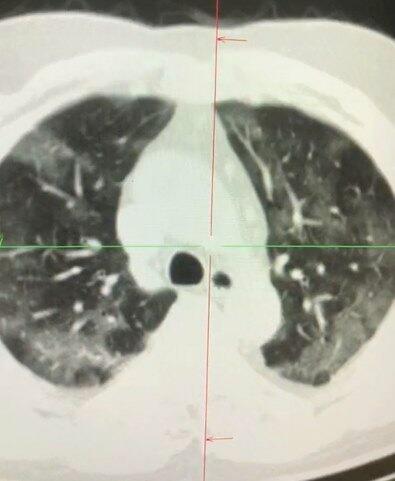

COVID-19 causes glaucoma syndrome in the lungs.

Axar.az reports that the statement came from medical professor Adil Geybulla.

Sharing his personal observations, the professor said that it was atypical pneumonia caused by the virus.